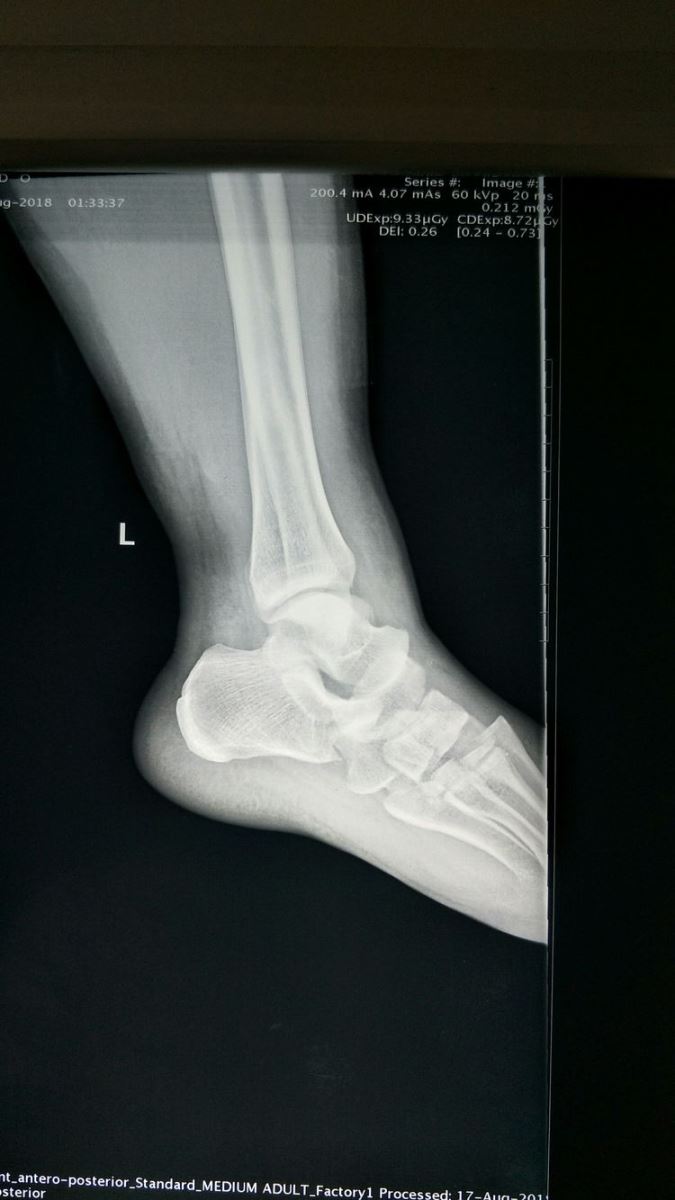

左踝关节侧位片:Chaopart关节脱位,跖跗关节脱位。

左踝关节正位片:前足向外侧移位。